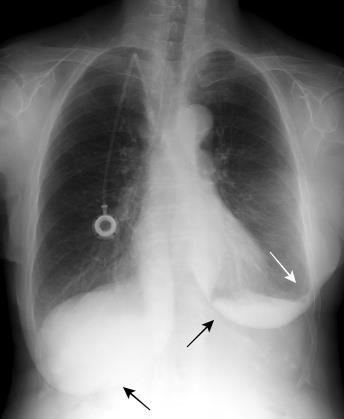

Neumonía por Estrept. neumonía. Derrame pericárdico. Empiema necesitatis (tubo de drenaje)

Edema de los tejidos extrapleurales subcostales (60%, 21 of 35).Takasugi et al. The extrapleural fat in empyema: CT appearance. Br J Radiol 1991